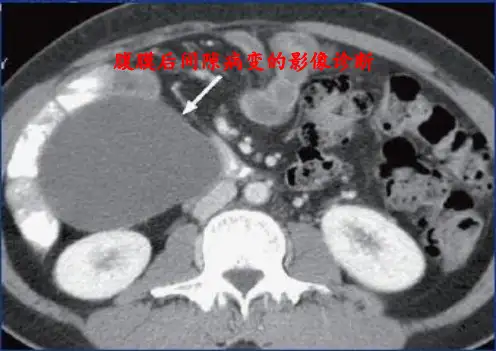

腹膜及腹膜后病变的CT诊断中南大学湘雅二院放射科黎凤媛一.腹膜的解剖及组织学:腹膜为被覆腹腔内面及脏器表面的一层浆膜,分脏层与壁层,壁层较厚,被覆于腹腔或盆腔内侧,光滑。

CT扫描检查密度分辨率高可弥补超声检查的不足,在腹水的衬托下,使用恰当的CT调窗技术可很好显示腹膜病变。

窗宽最好采用400-500HU。

必要时可以做多种窗技术扫描以帮助鉴别病变的性质及病理基础。

同时为了解胃肠道与腹腔内病变的相关性,在增强扫描前应口服造影剂和水。

采用高分辨率CT可提高腹膜的显示率。